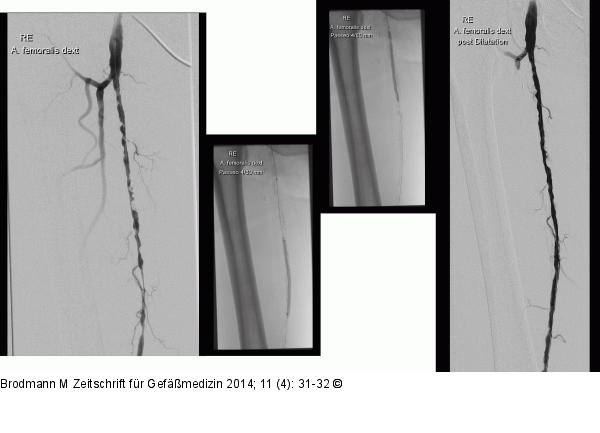

Abbildung 4: CTO-Revaskularisation Rekanalisation mit Navicross(R)-Katheter und Terumo Advantage(TM) 35, serielle PTA |

Rekanalisation mit Navicross(R)-Katheter und Terumo Advantage(TM) 35, serielle PTA |